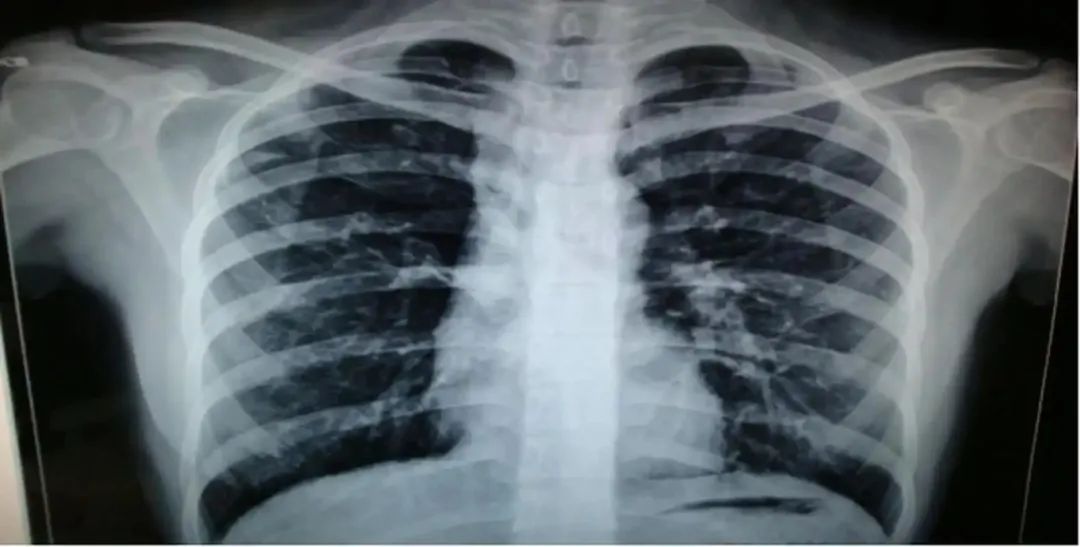

第二天一大早,王先生不情不愿的来到县医院体检中心,还特意做了肺部的CT。

"王先生,CT显示,您的肺中有结节,且有肺结节钙化灶。"

王先生拿着片子沉默了半分钟,才说出一句话:"真他妈神了!"